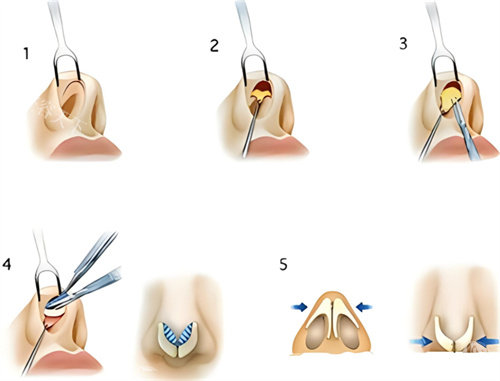

半肋软骨技术的核心优势在于“材料源于自身,塑形更贴合原生条件”。取用肋软骨中的柔性部分雕刻鼻尖支架,既能避免假体的异物感,又能精细控制鼻尖旋转度、延长鼻小柱。

沧州京美医疗美容鼻子整形术例中,主刀医生采用“悬浮鼻尖”雕刻法:将肋软骨削薄至0.8mm,分层叠加形成弹性支撑结构,术后鼻尖触感柔软,形态微翘而不僵硬。

仿生支架雕刻:肋软骨需保留天然弧度,模拟原生鼻中隔的力学结构;

小创口操作护航:通过鼻孔内切口植入材料,术后无可见疤痕。